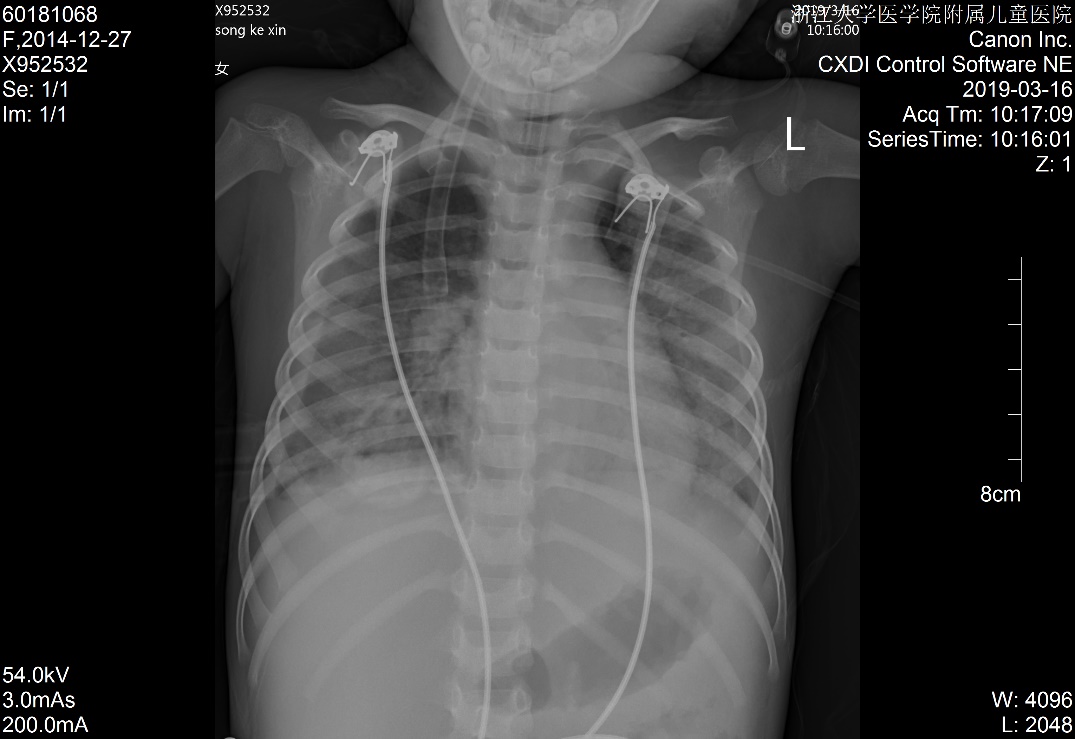

1 资料与方法患儿女,5岁2月,因“多尿、多饮、多食3个月余,意识不清1天余”由外院转入。3个月余前出现多尿、多饮、多食,家长未重视,未就诊。1 d前出现意识不清,并抽搐3次,急送当地医院就诊,当时查体情况具体不详,查血气电解质示pH 6.87,pCO225.9 mmHg,Na+ 125.4 mmol/L, Glu 17.1 mmol/L,Lac 1.1 mmol/L,HCO3- 4.6 mmol/L,ABE -28.1 mmol/L。考虑诊断“糖尿病、糖尿病酮症酸中毒、脑水肿?”收住当地医院。在当地医院住院期间,予大量补液[约3 L/24 h,大部分为晶体液,可能因为低血压,因住院期间曾使用多巴胺10 μg/(kg·min)维持],住院期间出现氧饱和度不能维持,遂予气管插管并机械辅助通气。因病情持续恶化,联系后转入本院PICU。既往史、个人史、出生史无殊。爷爷及外婆有糖尿病及高血压病。入院查体:T 37.8℃,脉搏:146次/min,呼吸:38次/min(为机械通气),血压98/77 mmHg(1 mmHg=0.133 kPa),无特殊面容及畸形,体质量:11 kg,气管插管带入,经皮血氧饱和度95%,镇静状态,双侧瞳孔等大等圆,直径2 mm,对光反射存在,颈软,余神经系统无明显阳性体征,面色苍白,消瘦貌,双肺呼吸音粗,可闻及湿啰音,腹软,肝脾肋下未及,皮肤弹性略差,肢端凉,毛细血管充盈时间5 s。入院后查白细胞计数8.52×109/ L-1,淋巴细胞15.4%,中性粒细胞82.0%,超敏C反应蛋白17.33 mg/L;血气分析:pH 6.996,pO2 91 mmHg, pCO2 43.5 mmHg,Na+ 126 mmol/L,Glu 21.0 mmol/L,Lac 2.9 mmol/ L,HCO3- 10.1 mmol/L,ABE -20.6 mmol/L;血氨63 μmol/ L;生化五类:总蛋白34.9 g/L,白蛋白26.5 g/L,丙氨酸氨基转移酶24 U/L,天门冬氨酸氨基转移酶96 U/L,肌酐147 μmol/L,尿素12.38 mmol/L,肌酸激酶1 680 U/L,肌酸激酶-MB活性166 U/L,甘油三酯6.05 mmol/L,胆固醇6.11 mmol/L,淀粉酶3 094.5 U/L;尿常规:尿酮体++,尿蛋白++,尿糖++++,尿隐血+++;糖化血红蛋白16.5%;血清C肽测定:0.116 nmol/L;糖尿病自身抗体阳性;脑脊液常规、生化及培养无殊;血尿培养阴性;胸片:两肺弥漫性病变,双侧胸腔积液,肺水肿待排(图 1);心超:左室收缩功能稍减低(EF 0.53),少量心包积液,二、三尖瓣轻度反流;腹部B超:肝大、腹腔积液。考虑诊断“急性呼吸窘迫综合征、急性肾功能损伤、1型糖尿病、糖尿病酮症酸中毒、脑水肿、多浆膜腔积液”,予呼吸机支持[HFO模式,FiO2:85%,f:5.8 HZ,ΔP:36 cmH2O(1 cmH2O=0.1 kPa),MAP:25 cmH2O, OI:23)、多巴胺及肾上腺素泵注维持血压、甘露醇降颅压、胰岛素注射降血糖及其他对症支持治疗,患儿入院第3天酮症酸中毒基本纠正,第6天改无创通气(CPAP,Flow:10 L/min,PEEP:4 cmH2O),入院第10天改大气吸入,复查胸片基本好转(图 2),住院期间未再抽搐,在停呼吸机机械通气镇静后意识好转,但较激惹、躁动,肾功能逐步恢复,住院28 d后出院,出院前患儿意识清,能完成日常对答,查头颅MRI提示脑萎缩改变,复查肺部影像学未出现遗留性病变,复查心超未见心包积液。现规律随访近一年,胰岛素治疗血糖控制尚可,未遗留明显神经系统、呼吸系统等后遗症。本研究经浙江大学医学院附属儿童医院伦理委员会批准(批准号:2020-IRB-078),并经患儿家属知情同意。

| 图 1 入院时胸片 |